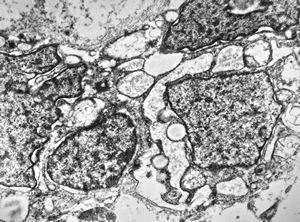

M,40y. | granular cell tumor

F,30y. | granular cell tumor